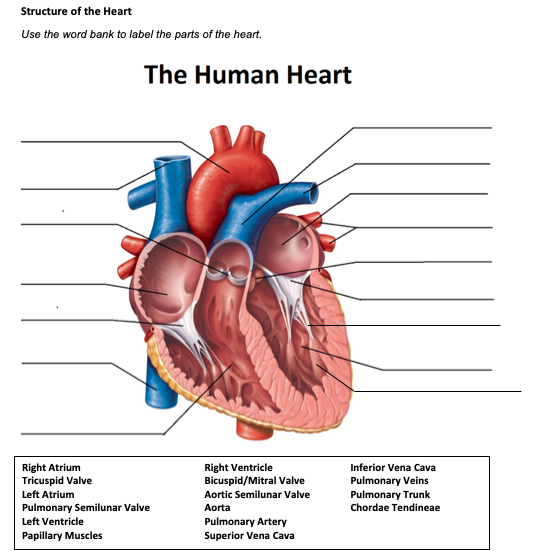

Anatomy of the tricuspid valve. The tricuspid valve complex consists of the annulus leaflets right ventricle papillary muscles and chordae tendinae. Right atrioventricular valve tricuspid valve these are large veins that transport deoxygenated blood from the body back to the heart.

B the relevant anatomy shown from the front view. The tricuspid valve lies between the right atrium and the right ventricle and is placed in a more apical position than the mitral valve. The tricuspid valve has an area of 4 to 6 cm square and is located between the right atrium and the right ventricle of the heart.

The valve has anterior posterior and septal leaflets cusps the bases of which attached around the av orifice to the fibrous ring fibrous skeleton of the heart. Blood collects within the right atrium and it must flow through the tricuspid valve in order to enter the right ventricle. The tricuspid valve functions as a one way valve that closes during ventricular systole to prevent regurgitation of blood from the right ventricle back into the right atrium.

Solved Structure Of The Heart Use The Word Bank To Label

Solved Structure Of The Heart Use The Word Bank To Label